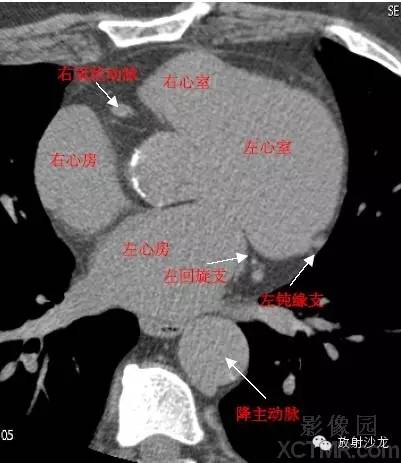

D. Aorta-Descending Aorta降主动脉

LAD -Left Anterior Descending Artery左前降支

LCX -Left Circumflex Artery左回旋支

LMB -Left Obtuse Marginal Branch 左边缘支(钝缘支)

RCA -Right Coronary Artery 右冠状动脉

GCV–Great Cardiac Vein心大静脉